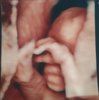

Młody ma się dobrze, dosłownie wsio okej, więc nie wymieniam, nawet dość ładnie buziaka pokazał do zdjęć, nasze małe ufo